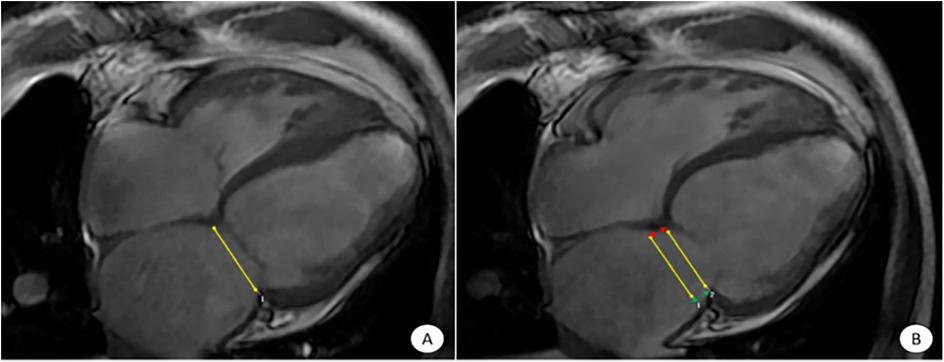

Figure 1

CVI42 software for automatic acquisition of MAPSE at the four-chambered core level of the movie. The CVI42 software automatically traces the measurement of MAPSE at the 4CH level, (A) end-systolic mitral annular plane; (B) diastolic mitral annular plane. The MAPSE [distance between the two yellow lines in (B)] reflects LV function and LV long-axis motion. Lateral MAPSE refers to the distance between the lateral wall attachment points of the mitral valve in systole and diastole [between the two green arrows in (B), 6.1 mm], and Septal MAPSE refers to the distance between the septal attachment points of the mitral valve in systole and diastole [between the two red arrows in (B), 7.4 mm]. MAPSE, systolic displacement of mitral annular plane.

Select the 3D short-axis and long-axis modules for routine cardiac function parameter analysis, import short-axis movie images in the short-axis and select the four-chamber heart as the reference plane, import two-chamber and four-chamber heart movie images in the long-axis, and then click on the AI operation button to automatically outline the endo-epicardial and epicardial boundaries from the base of the heart to the apex of the heart, and then the software analyzes the cardiac function indexes such as the left ventricular ejection fraction (LVEF), the lateral MAPSE, and the septal MAPSE (Figure 1).